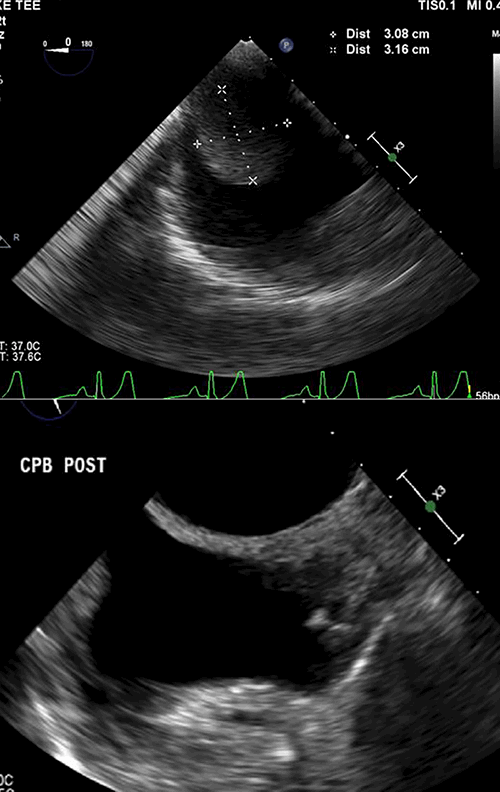

She underwent an echocardiogram, which revealed a large mass in the right atrium extending into the inferior vena cava (IVC) (Figure 1).

Figure 1: Echocardiogram performed at presentation, showing the right atrial mass.

After gaining control of the infrarenal IVC, the right and left renal veins, and the right adrenal vein, the right lobe of the liver was mobilized, and the supra-hepatic IVC was cleared and readied for vascular control. The cardiac team then put the patient on cardiopulmonary bypass and opened the right atrium. The tumor thrombus was evident, as depicted on the intraoperative TEE (Figure 3A). With control of the IVC, the left renal vein was opened lengthwise near its IVC insertion. The tumor thrombus was gently pushed downwards digitally through the atrial incision into the IVC and gently pulled from below and delivered into the venotomy of the left renal vein in its entirety. The tumor was not adherent to any structures. Blood flow around the IVC/renal vein venotomy was controlled manually with pressure and vessel loops while the cardiac surgeons closed the atrium and took the patient off cardiopulmonary bypass (Figure 3B).

Figure 3: Intraoperative transesophageal echocardiogram before (A) and after (B) tumor resection

The renal vein was opened along its length to deliver the large tumor thrombus back to the adrenal vein, which was then transected, and the entire tumor along with its intravascular extension was removed in one piece (Figure 4). The renal vein and IVC were closed, with return of normal blood flow to the left kidney and IVC. TEE showed a normal right atrium and IVC. The patient remained hemodynamically stable. Total blood loss was less than 600cc.